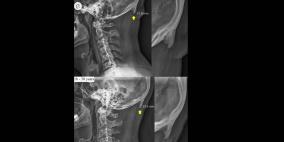

"شوكة الجمجمة"..الخطر الأكبر على مستخدمي الهواتف الذكية